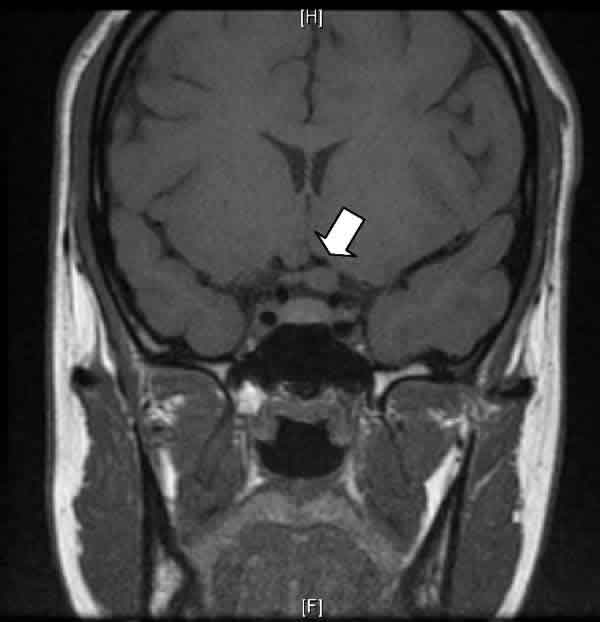

Una mujer de 20 años, con antecedentes de depresión mayor y ansiedad generalizada, acudió a consulta por pérdida de visión del ojo izquierdo (OI). La paciente refería que si bien la agudeza visual (AV) del OI había sido siempre muy baja, en los últimos meses notaba cierto empeoramiento visual. En la exploración, la AV del ojo derecho (OD) era de 1,0 (–4 –0,75 a 10º) y la del OI, 0,05 (–13,5 –4 a 5º). La exploración del segmento anterior sólo reveló una mínima opacidad subcapsular cristaliniana del OI. Funduscópicamente, se observaba una gran retinocoroidosis miopica en el OI. Se le diagnosticó de ambliopía profunda OI por anisometropía agravada por una catarata subcapsular incipiente en ese ojo. Se le remitió a Atención Primaria con la recomendación de revisiones oftalmológicas periódicas. Sin embargo, a los 4 meses, la paciente experimentó un cuadro autolimitado de alucinaciones auditivas («oía discusiones» y «voces que comentaban sus pensamientos»), por lo que fue valorada psiconeurológicamente. Al tratarse de síntomas atípicos de un trastorno afectivo, y para descartar un origen orgánico, se le realizó una resonancia magnética cerebral que evidenció la existencia de un engrosamiento de nervio óptico izquierdo localizado en su porción más posterior y en la región adyacente del quiasma óptico, muy sugestivo de glioma óptico (figs. 1 y 2). Reevaluada oftalmológicamente, la AV mejor corregida del OI se mantenía en 0,05, y la papila óptica del OI tenía un aspecto ligeramente pálido, difícil de valorar por las alteraciones miópicas (fig. 3). Campimétricamente, se objetivó una depresión generalizada del OI sin afectación del OD. La exploración neurológica no aportó ningún otro hallazgo, y en la dermatológica no se encontró ningún signo de neurofibromatosis tipo 1 (NF-1).

Fig. 2: En este corte coronal en modo T1, se objetiva el agrandamiento de la sección del nervio óptico izquierdo (flecha).